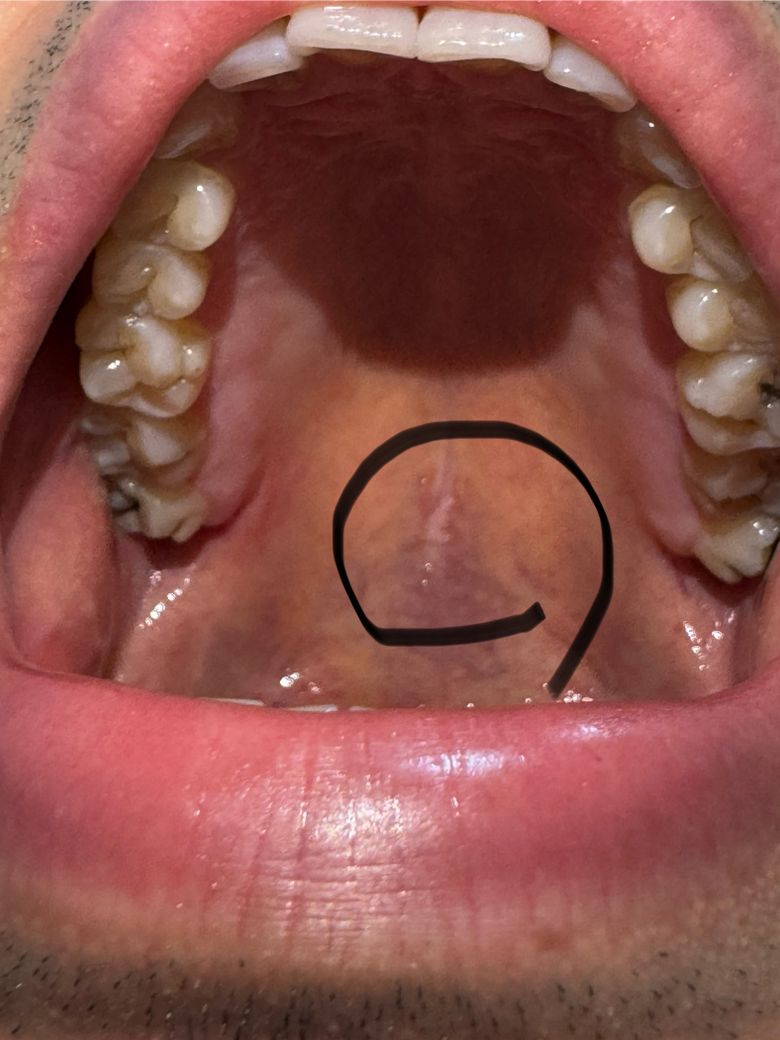

입천장에 하얀색같은게있는데요….

입천장 가운데가 햐얗게 되어있는데

원래 이런건지

아니면은 병원을 가봐야하는지

통증은 전혀없습니다.

• 2번 째 사진

사람마다 조직의 형태는 다를 수 있습니다. 염증 등의 소견은 없어보이며 걱정할 건 아닌 것 같습니다.

입천장이 뜨거운거나 자극적인 음식등에 화상을 입은거 같습니다. 큰문제가 잇는건 아니니 당분간 자극이 가지 않도록 해주시는게 좋습니다.

사진으로는 정확한 확인이 어려워 보입니다. 입찬장에는 오톨도톨한 돌기가 있는데 이런 부분들이 하얗게 보이는 할 수 있습니다.

대부분 큰 문제가 되는 것은 아니기 때문에 너무 걱정하지 않으셔도 될 것으로 생각됩니다. 자세한 확인을 위해서 치과에서 진료를 받아보는 것을 권유드립니다.

입천장 형성과정에서 양쪽 입천장이 가운데쪽으로 자라면서 서로 근접하면 유합되게 됩니다. 그 유합선의 흔적이고 특별히 이상한 점은 없는 것 같습니다.